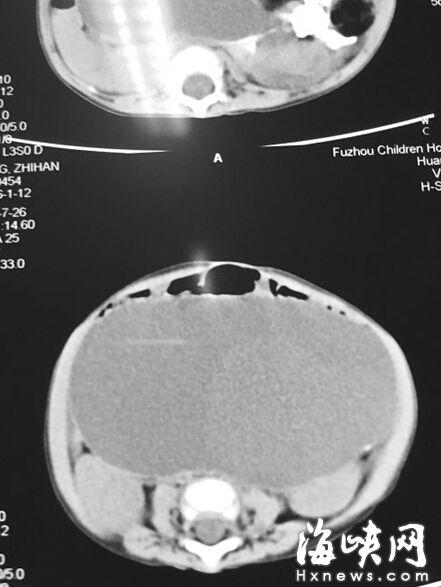

CT顯示,小云腹腔被畸胎瘤霸占

7月22日,家人抱著小云到福州兒童醫(yī)院,福州兒童醫(yī)院副院長(zhǎng)、小兒外科學(xué)博士林芃一摸她肚子,推斷可能是巨結(jié)腸或腫瘤。果然,B超結(jié)果顯示,小云 的左側(cè)腹膜后藏著一個(gè)巨大腫瘤,被腸管擋住了,為此多次漏診。腫瘤直徑約20厘米,幾乎霸占整個(gè)腹腔。7月29日,醫(yī)生花了3個(gè)小時(shí)剝離腫瘤,其皮質(zhì)硬。 醫(yī)生將瘤中的液體吸出500多毫升,“排球”癟了1/3,才被順利取出。這是一個(gè)畸胎瘤,足有2斤重,這么大的很罕見(jiàn)。但畸胎瘤分化不成熟,沒(méi)有成形的毛 發(fā)、牙齒等組織,很可能是惡性腫瘤,目前還在等病理報(bào)告。